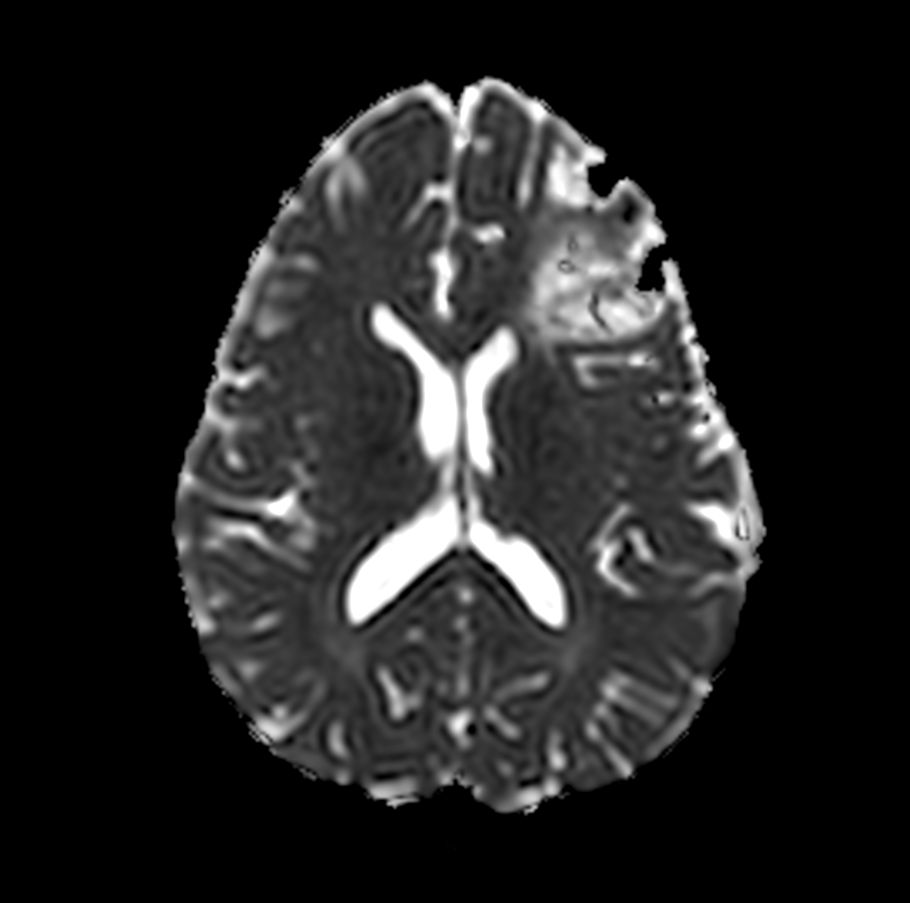

Axial DWI b1000

Axial DWI b1000 (ADC)